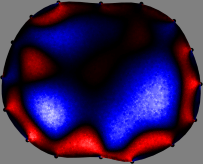

Figs. 3 and 4 compare the performance of the proposed FER method in (20) with the standard regularized least-squares method ((19) when is the identity matrix). The regularization parameter of the standard method was heuristically chosen for its best performance, and the parameter of the FER method was set to be one of three different values . The injection current was 1 mA at 100 kHz, and the frame rate was 9 frames per second. The reference frame at was obtained from the maximum expiration state. The measured data, , represent the voltage differences between each time and . The blue regions, which denote where conductivity decreased by inhaled air, increased during inspiration and decreased during expiration. The FER method with was clearly more robust than the standard method that produced more artifacts originated from the inversion process.

| Standard | |

||||||||||

| FER () | |